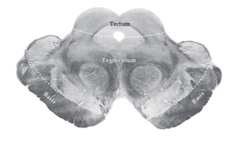

What are the 3 regions of the mesencephalon?

A

tectum

tegmentum

basis pedunculi